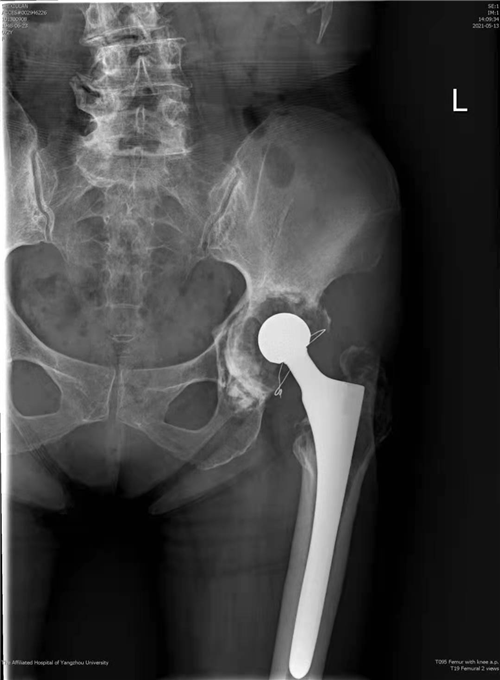

近日,我院骨科关节组副主任医师徐松诊疗团队成功为一名髋关节假体松动患者实施了全髋关节翻修手术。该手术为我院首次独立完成,打破了我院髋关节翻修需请上级专家会诊或转上级医院手术的传统,填补了我院关节技术的空白,为扬州地区髋关节假体松动患者的治疗提供了便利、减轻了经济负担,为该类患者带来了福音。

据了解,患者73岁,女性,7年前因创伤性股骨头坏死接受左全髋关节置换手术治疗,术后髋关节活动一切如常,近3年来患髋逐渐出现疼痛、活动受限,患者渐渐不能行走,长期卧床。因手术难度大、风险高,患者辗转扬州多家医院均遭拒,或建议其上级医院就诊。患者来到我院骨科,接受左全髋关节翻修手术,术后第四天即可下地正常活动,恢复后的患者激动地说:“躺了2年多,我终于可以自己站起来了!”

骨科副主任医师徐饶介绍,人工髋关节置换是我院常规开展的一种手术,但人工假体有使用寿命,经长期不规范使用后假体会出现松动,进而进一步影响髋关节功能,情况严重的患者只能长期卧床,患者生活质量受到严重影响,因此需要再次对人工髋关节进行翻新修复,以恢复髋关节的功能。因为人工髋关节的功能是建立在人工假体的稳定性及周围软组织平衡性基础之上,所以对局部骨量及软组织质量要求都比较高,然而松动的假体往往会破坏局部正常的骨结构,引起局部骨量流失,加之初次手术造成的大量骨质缺失、疤痕粘连、软组织解剖结构异常,该类手术难度往往非常大。现在,经过多年技术的积累与沉淀,我院骨科关节组已经完全具备了独立开展此类手术的技术条件,造福了更多扬州百姓。